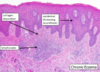

atopic eczema

lupus erythematosus

Anti DNA Antibodies (ANA)

may affect any organ, butterfly malar rash, female>male, african american >